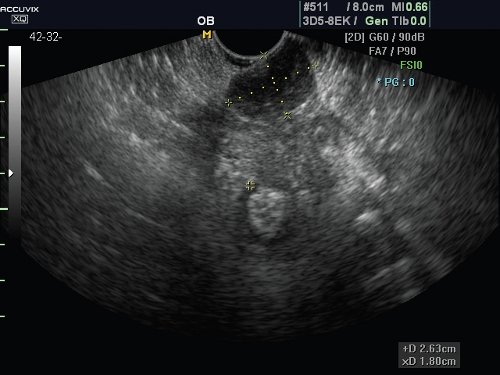

Из послеоперационных осложнений после применения различных хирургических технологий диагностированы гематомы разной локализации. Бесспорной и однозначной эхографической диагностике доступны гематомы тазового дна после перинеолеваторопластики. Имели клиническое значение и требовали дополнительного лечения гематомы размером более 40 мм (рис. 2); патологические образования меньшего размера протекали благоприятно и спонтанно полностью рассасывались к 30-45 сут послеоперационного периода (рис. 3). Деформации мышечных пучков, нарушения анатомии тазового дна в этих случаях не было выявлено. Гематом стенок влагалища после кольпоперинеолеваторопластики не было выявлено.

Рис. 2. Параректальная гематома.

Рис. 3. Гематома после перинеолеваторопластики.